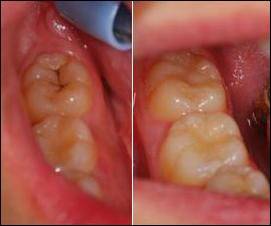

다음은 여성 분들이 좋아하는 레진이다. 레진의 가장 큰 장점은 심미적이라는데 있다.

왼쪽 사진을 보지 않는다면 오른쪽 사진에서 원래 충치가 있던 부분을 찾기는 쉽지 않을 것이다.

또 다른 레진의 장점으로는 치아의 삭제량이 적다는 점이다. 레진은 접착제를 이용해서 붙이기 때문에 특정한 모양으로 깎을 필요 없이 충치가 생긴 부위만 제거해내면 된다. 그래서 건전한 치질의 손실이 적다는 점이 레진의 장점이다.